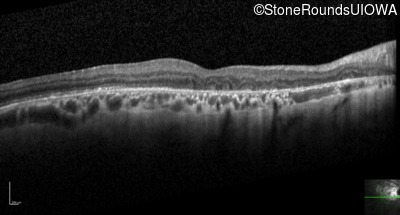

Optical Coherence Tomography - Left - 20/200

Exemplar / OCT Stack